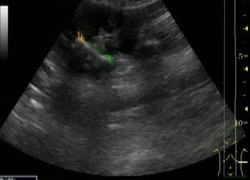

Рис. Ультразвуковое исследование.